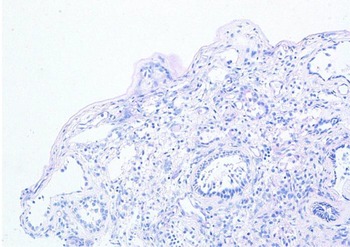

The mucosal biopsy sections measured 8 mm × 4 mm in maximum dimension. There was extensive loss of surface epithelium (Figure 2), with no associated surface fibrin or inflammatory exudate (Figure 3). The architecture of glands in the lamina propria was maintained. A minimal chronic lymphocytic inflammatory infiltrate was present (Figure 2). No eosinophils or mast cells were identified.

Fig. 3. Special stain does not highlight surface basement membrane or inflammatory exudate. (Periodic acid–Schiff; ×100)